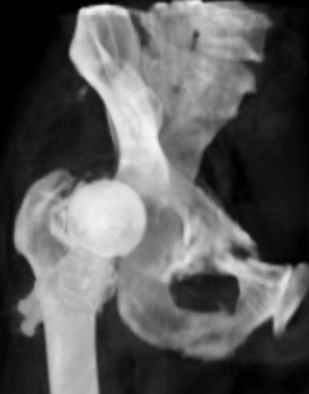

Уважаемые коллеги,Мужчина 1952 г.р. поступил в 36 больницу Екатеринбурга 1 июня 2004 г. Диагноз: Множественный перелом ребер слева, субтотальный гемоторакс, оскольчатый перелом шейки правого бедра.Повреждение таза не диагностировано. 17 июня 2004 г. - открытый остеосинтеза шейки бедра винтами с костной аутопластикой. Заживление раны первичное. Выписан 1 июля. 4 июля отметил укорочение конечности. При контрольном осмотре через 1 месяц после остеосинтеза - передний вывих бедра. Неправильно срастающийся перелом костей таза.Вопрос - особенности эндопртезирования тазобедренного сустава в этой ситуации?

ВМТ> осмотре через 1 месяц после остеосинтеза - передний вывих бедра.

Не из-за того, что передние структуры сустава не восстановили?

Перелом там от бокового сжания, похоже на LC-I, т.е. компрессионный перелом крестца и на этой же стороне лонной и седалищной. Впадина выглядит совершенно целой. Если там и есть какая-то импрессия в переднем отделе - то микроскопическая.

Надо, наверно, какие-то меры принимать от такого же переднего вывиха протеза.